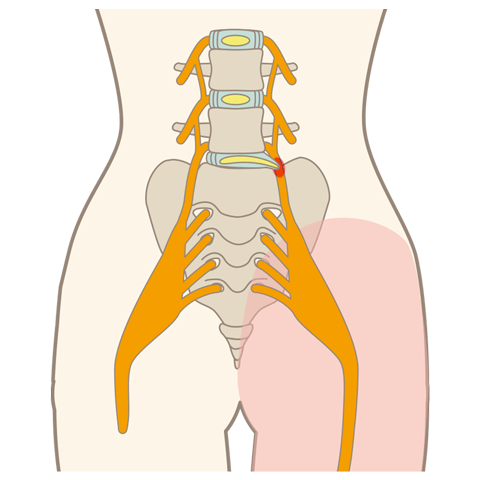

腰のMRI検査です。複数箇所で椎間板容量が低下しており、脊柱管狭窄症も認めます。

検査により損傷部分を確定させてディスクシール治療を行っているところになります。

腰部脊柱管狭窄症とは、背骨にある神経の通り道「脊柱管」が狭くなる疾患です。腰痛や足の神経障害、歩行困難などの症状を引き起こします。

坐骨神経痛

坐骨神経痛とは、腰椎椎間板ヘルニアや腰部脊柱管狭窄症などを原因とし、腰から下部の臀部や脚部に痛みや痺れを感じる症状です。